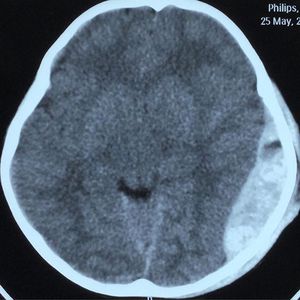

Massive epidural hematoma ( volume : 96,4 cc), a young boy admitting to ER with LOC after RTA. Note the swirl sign indicating there is a on going bleeding